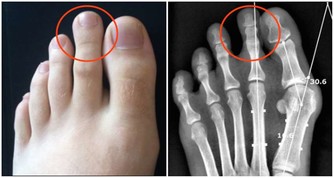

3.引發胃病

長期飲食不規律,很晚才吃晚飯,也會增加患消化系統疾病的概率。

比如有些人中午吃過飯以後要到晚上九、十點鐘才會再吃飯,

導致食物在身體內消化得不夠充分,這一類人很容易得胃炎、潰瘍病這樣的健康問題。